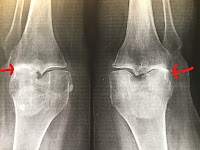

I have terrible arthritis in both knees—“bone on bone,” as they say. You can see the bone-on-bone part in the photo below (as pointed out in my poorly-drawn arrows).